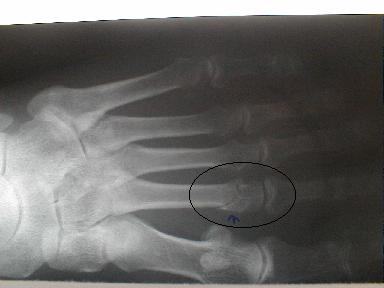

8月13日

整復方法

末梢方向に持続牽引し側方圧を加え完了

受傷時8月6日のx-pでは骨折が確認出来ずに他の医院で打撲として治療していたもので、再度x-pを撮ったところ骨折が確認できた固定をしなかった為に骨に無理な力が加わったものと思われる。固定の重要性が認識される。

| 9月10日固定除去し9月30日経過良好にて治癒とす |